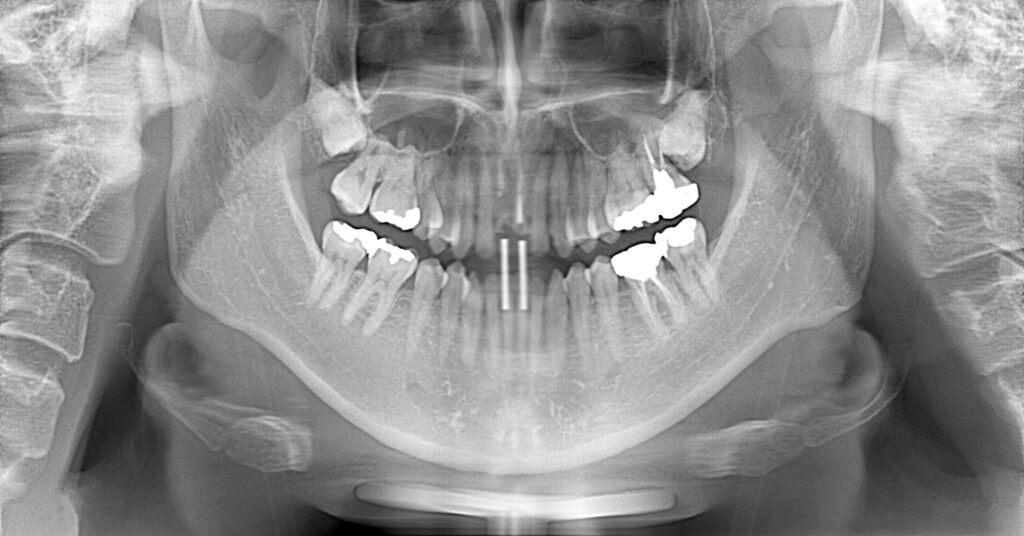

症例一覧 インプラント症例3 2024.11.25 治療内容インプラント主訴前歯部折れたのでインプラント治療を行いたい費用¥1259,500(2本)治療期間治療期間 7ヶ月 インビザライン症例1 前の記事 インプラント症例2 次の記事